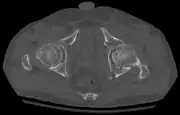

Axial CT image (viewed on bone windows) of a complex comminuted left acetabular fracture involving both anterior and posterior columns.